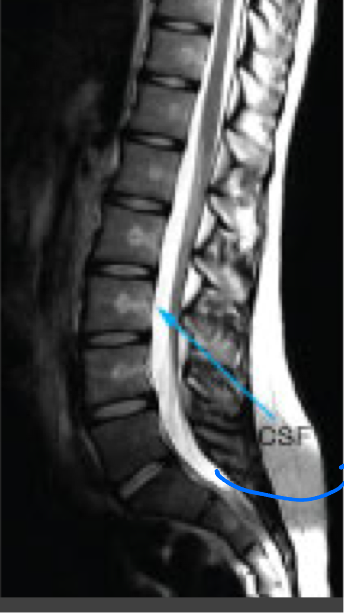

MRI: T1 weighted images

Highlights fat as bright

Muscles as intermediate

Water (blood, CSF) as dark

MRI: T2 weighted images

Highlights water as bright

Fat as slightly less bright

Muscle as intermediate

Brain- white matter is darker than gray matter

Spine MRI

—evaluating soft tissues of the spine, disc herniations and spinal cord injuries, fractures are usually evaluated by CT